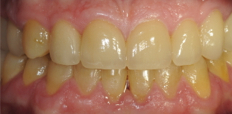

ПОСЛЕ

Проведено лечение брекет-системой, установлены имплантаты в жевательном отделе, изготовлены виниры и безметалловые коронки на зубы в зоне улыбки, восстановлена дикция, устранены морщины в уголках рта.